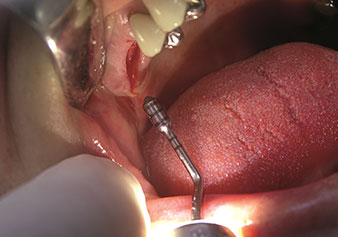

One application, which is often underestimated is the atraumatic extraction of tooth roots or root fragments in the scope of alveolar management. The fine periotomes, which are currently available in two versions (EX1 and EX2 from W&H), can also be used to remove teeth which have previously undergone special endodontic treatment or ankylosed roots with ease. This results in extraction alveoli where both the hard and soft tissue are fully intact as it is generally possible to avoid reflection.

This establishes the optimal basis for subsequent or immediate implant treatment (Figures 1 and 2 included with the kind permission of Dr Torsten Conrad, Bingen a. Rhein).

Situation following piezosurgical extraction

Fig. 2: Situation following piezosurgical extraction. Photo: © Dr Torsten Conrad (Bingen am Rhein)